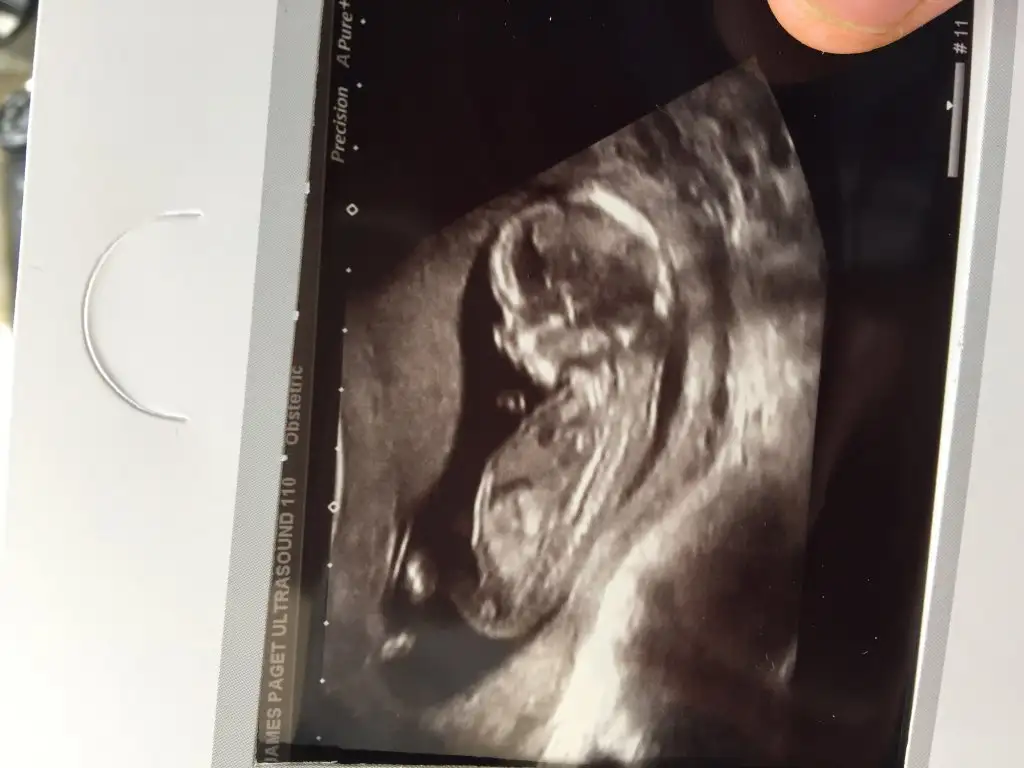

kızlar cinsiyet tahmini yapabilen var mı :)

Eklentiler

• tp10.webp

tp10.webp

11,6 KB · Görüntüleme: 119

• tp7.webp

tp7.webp

10,6 KB · Görüntüleme: 122